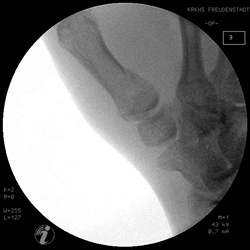

Basisfraktur des 1. Mittelhandknochen

Wenn die Frakturstellung nach Reposition und Ligamentotaxis

gut ist, kann die Fraktur mit einem gelenküberbrückenden Microfixateur

stabilisiert werde.

Die Frakturkontrolle muß in allen Ebenen kontrolliert

werden.